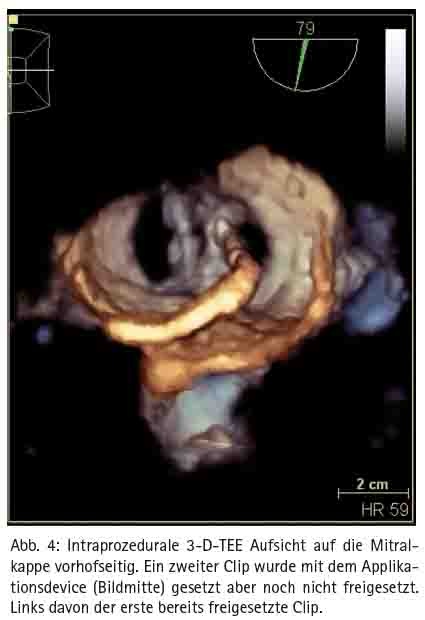

Der Eingriff erfolgt im Herzkatheterlabor unter Röntgendurchleuchtung und transösophagealer Echokardiographie und dauert ca. 60 Minuten (Abb. 5). Wegen der transösophagealen Echokardiographie ist eine Analgo-Sedierung oder intravenöse Kurznarkose sinnvoll. Der Zugang erfolgt über eine Leistenvene. Anschließend wird eine transseptale Punktion durchgeführt. Dann wird selektiv ein Katheter in das linke Vorhofohr vorgeführt und eine Angiographie in mehreren Ebenen zur Größenbestimmung und Beurteilung der Anatomie durchgeführt. Nach der ermittelten Größe und anatomischen Vorgabe erfolgt die Deviceauswahl. Derzeit stehen folgende drei Occluder zur Verfügung: Watchman, Amplatzer Cardiac Plug und Amulet. Im Weiteren wird die Device-Schleuse im linken Vorhofohr positioniert. Durch die Schleuse wird das gefaltete Device in das Vorhofohr vorgeschoben und freigesetzt. Eine orale Antikoagulation ist als Nachbehandlung nicht mehr nötig. Die Patienten erhalten nach individueller Maßgabe für die drei bis sechs Monate eine duale Thrombozytenaggregationhemmung. Eine antibiotische Endokarditisprophylaxe sollte für sechs Monate durchgeführt werden.